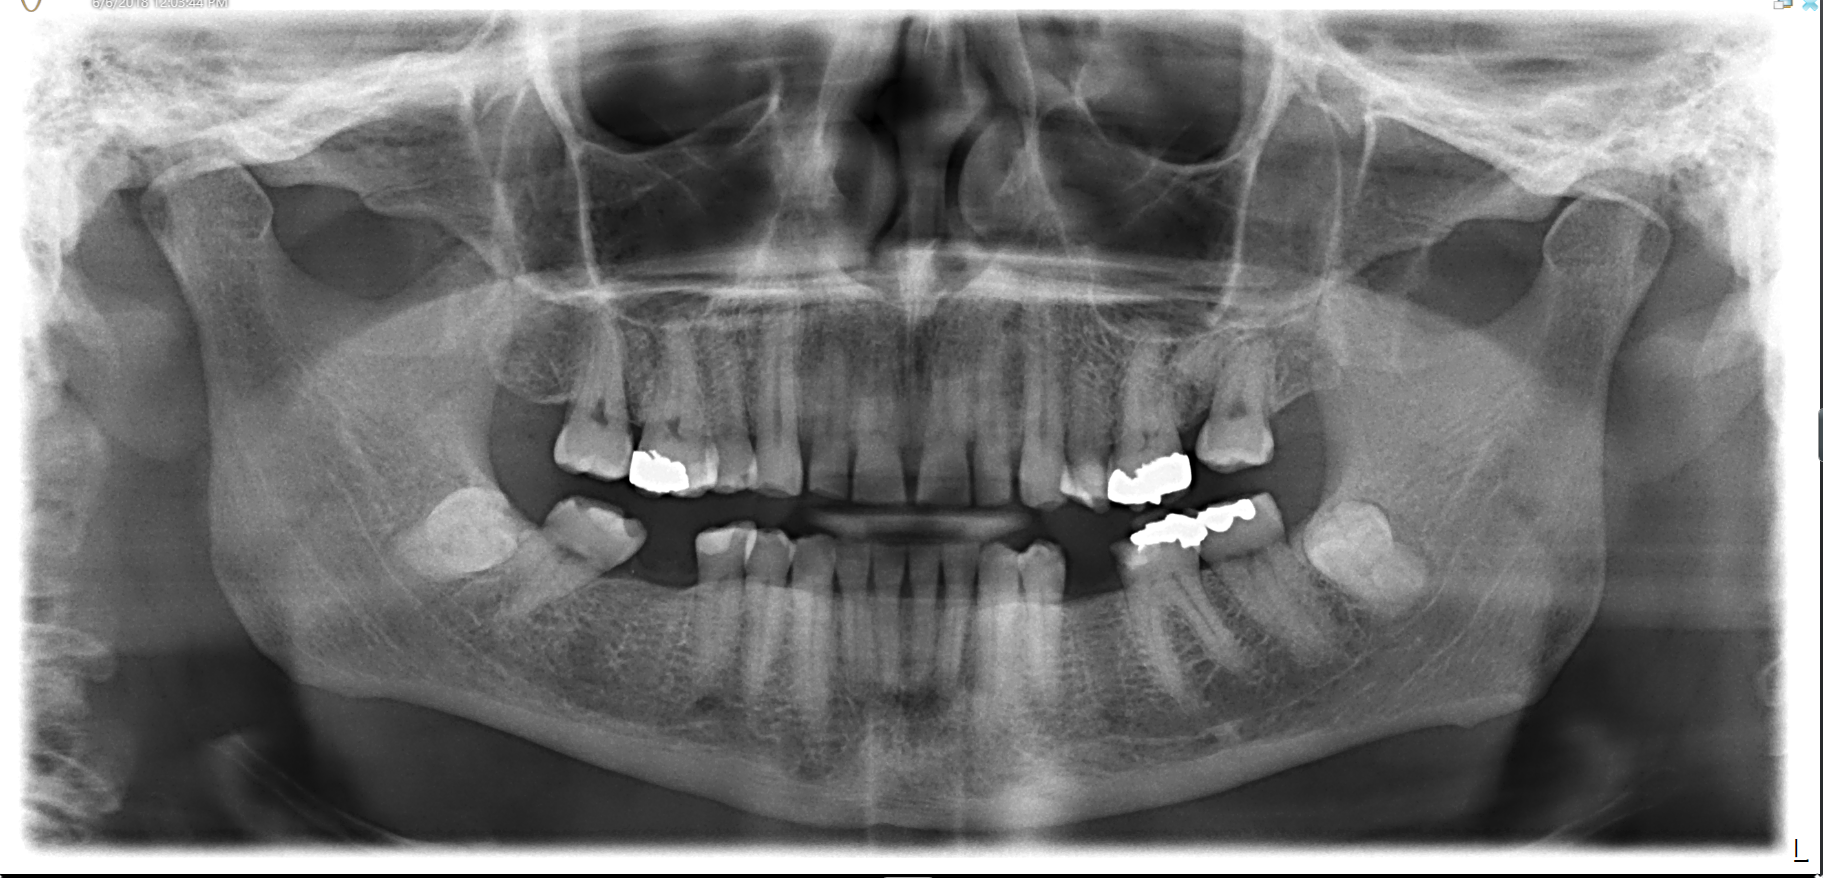

We start with a comprehensive full mouth examination, digital X-rays, a dental 3D(CBCT) scan and Trios5 Scan. The scanned images provide high-resolution images in a three dimensional plane. We use these images and scans for precise treatment planning.

CBCT 3D Scan